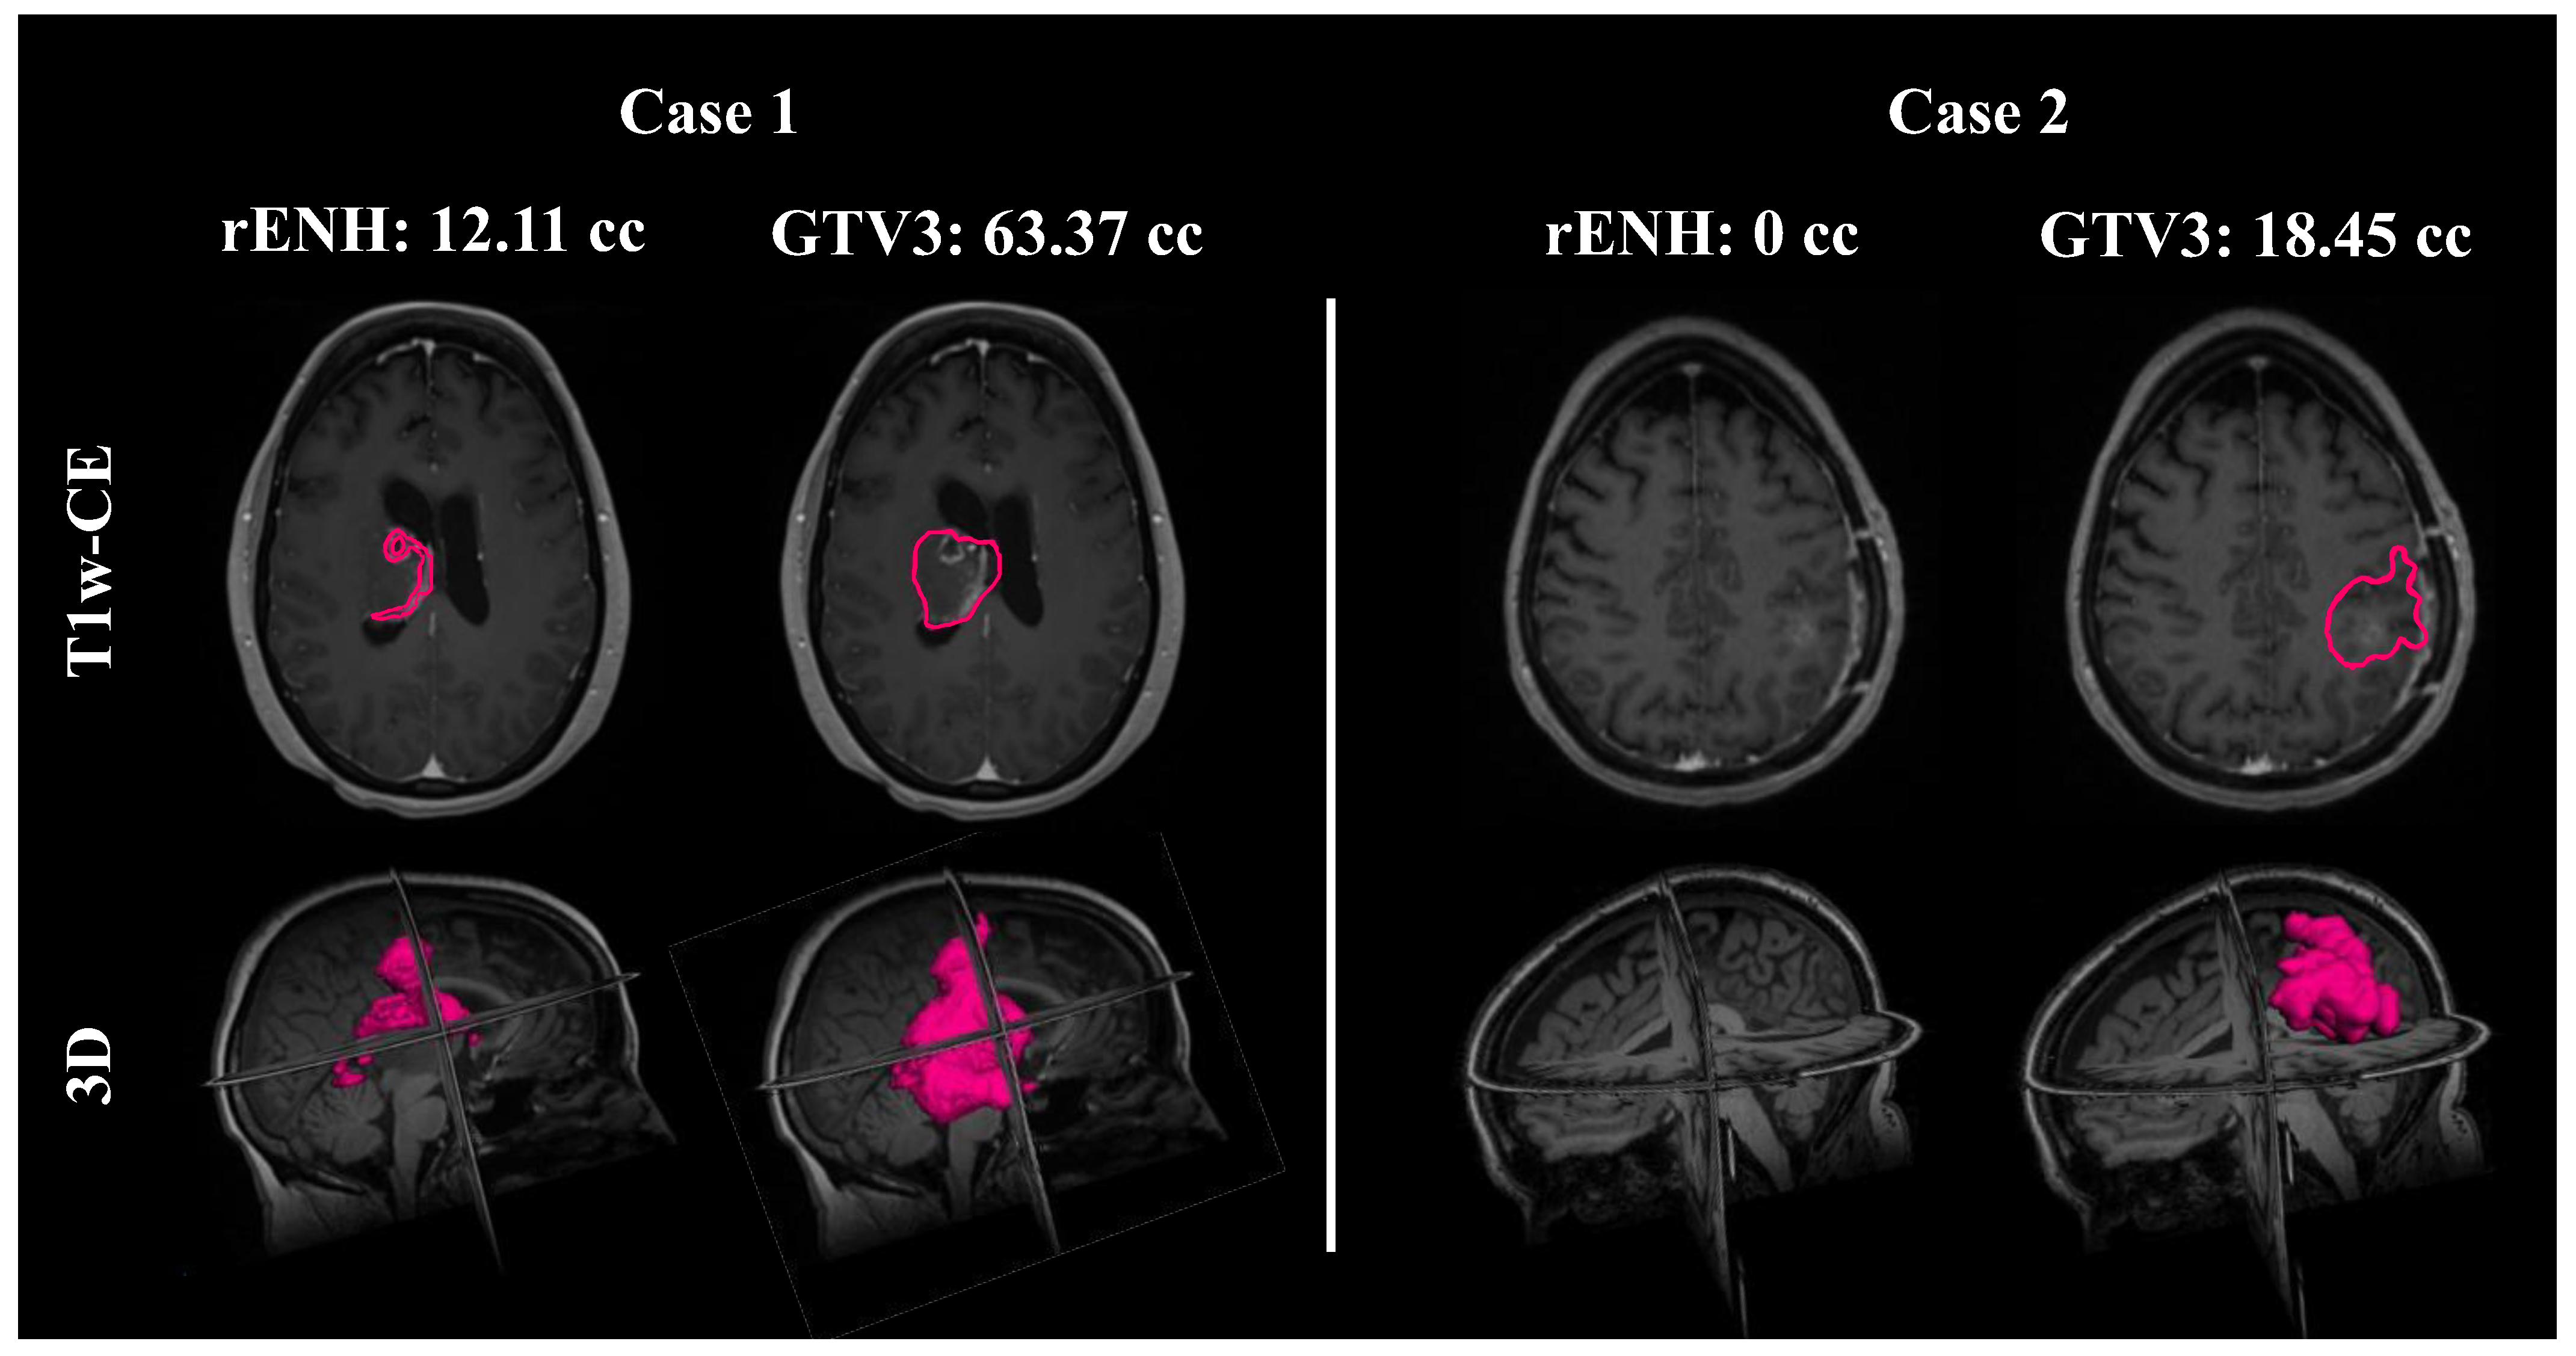

In Figure 2, two subjects are shown; Case 2 is the same patient shown in Figure 1. The vast difference in rENH and GTV3 contour volumes for the two subjects is shown here, particularly in Case 2 where the volume of residual enhancement was 0 cc. Both contours are also rendered in 3D to emphasize the spatial differences between the rENH and GTV3 contours.

Figure 2.

Two sample cases are shown. In the first case, the first column shows the residual post-contrast enhancement (rENH) contour (pink outline) with a volume of 12.11 cc, overlaid on the T1-weighted contrast-enhanced (T1w-CE) MRI (first row) for a 54-year-old female glioblastoma patient. The second column shows the gross tumor volume 3 (GTV3) contour (pink outline), over 5 times larger than rENH with a volume of 63.37 cc. The second row is a three-dimensional rendering of both contour volumes overlaid on a T1 pre-contrast image. In the second case of a 56-year-old female glioblastoma patient, there is no residual contrast enhancement visible on the T1w-CE MRI, whereas the GTV3 volume is 18.45 cc.